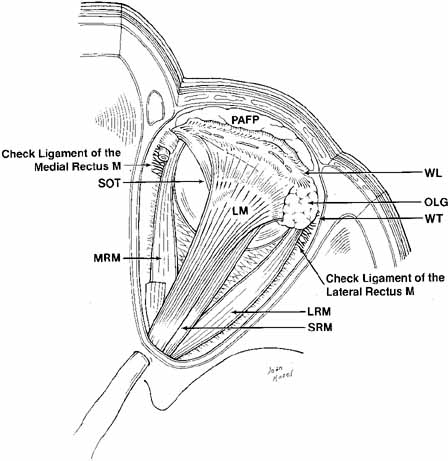

Fig. 11 Superior view of the orbit. Whitnall's ligament fuses medially with

the trochlea of the superior oblique muscle and fuses laterally with

the lacrimal gland. The medial horn of the levator aponeurosis lies directly

on top of the superior oblique reflected tendon. The lateral horn

of the levator aponeurosis splits the palpebral and orbital lobe of

the lacrimal gland. The lateral rectus check ligament attaches to Whitnall's

tubercle and is slightly denser than the medial rectus ligament. (WL, Whitnall's ligament; OLG, orbital lobe of lacrimal gland; SOT, superior oblique tendon; PAFP, preaponeurotic fat-pad; LM, levator palpebrae superioris muscle; WT, Whitnall's tubercle; MRM, medial rectus muscle; LRM, lateral rectus muscle; SRM, superior rectus muscle) Fig. 11 Superior view of the orbit. Whitnall's ligament fuses medially with

the trochlea of the superior oblique muscle and fuses laterally with

the lacrimal gland. The medial horn of the levator aponeurosis lies directly

on top of the superior oblique reflected tendon. The lateral horn

of the levator aponeurosis splits the palpebral and orbital lobe of

the lacrimal gland. The lateral rectus check ligament attaches to Whitnall's

tubercle and is slightly denser than the medial rectus ligament. (WL, Whitnall's ligament; OLG, orbital lobe of lacrimal gland; SOT, superior oblique tendon; PAFP, preaponeurotic fat-pad; LM, levator palpebrae superioris muscle; WT, Whitnall's tubercle; MRM, medial rectus muscle; LRM, lateral rectus muscle; SRM, superior rectus muscle)

|